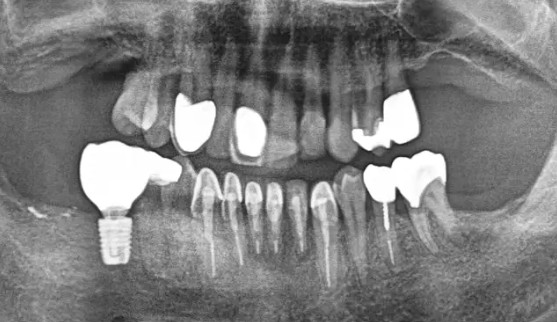

画像所見

CTにて、欠損部の骨幅・骨高ともに十分。

上顎洞までの距離にも余裕があり、骨造成(サイナスリフト)は不要と判断。

骨密度も良好で、1本のインプラントで十分な支持が得られる条件が整っていました。

渥美先生はCTを見せながら、「この骨の厚みがあれば、1本でしっかり噛める」と説明。

過剰な外科手術の必要がないことを丁寧に解説しました。

骨量十分。インプラント1本で設計決定。